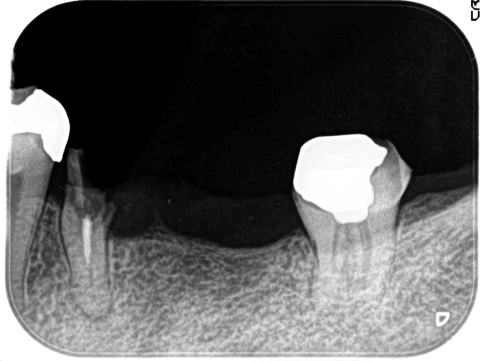

造骨後のレントゲン写真

インプラント植立前に、骨の量を垂直+頬舌方向に高く太くします。